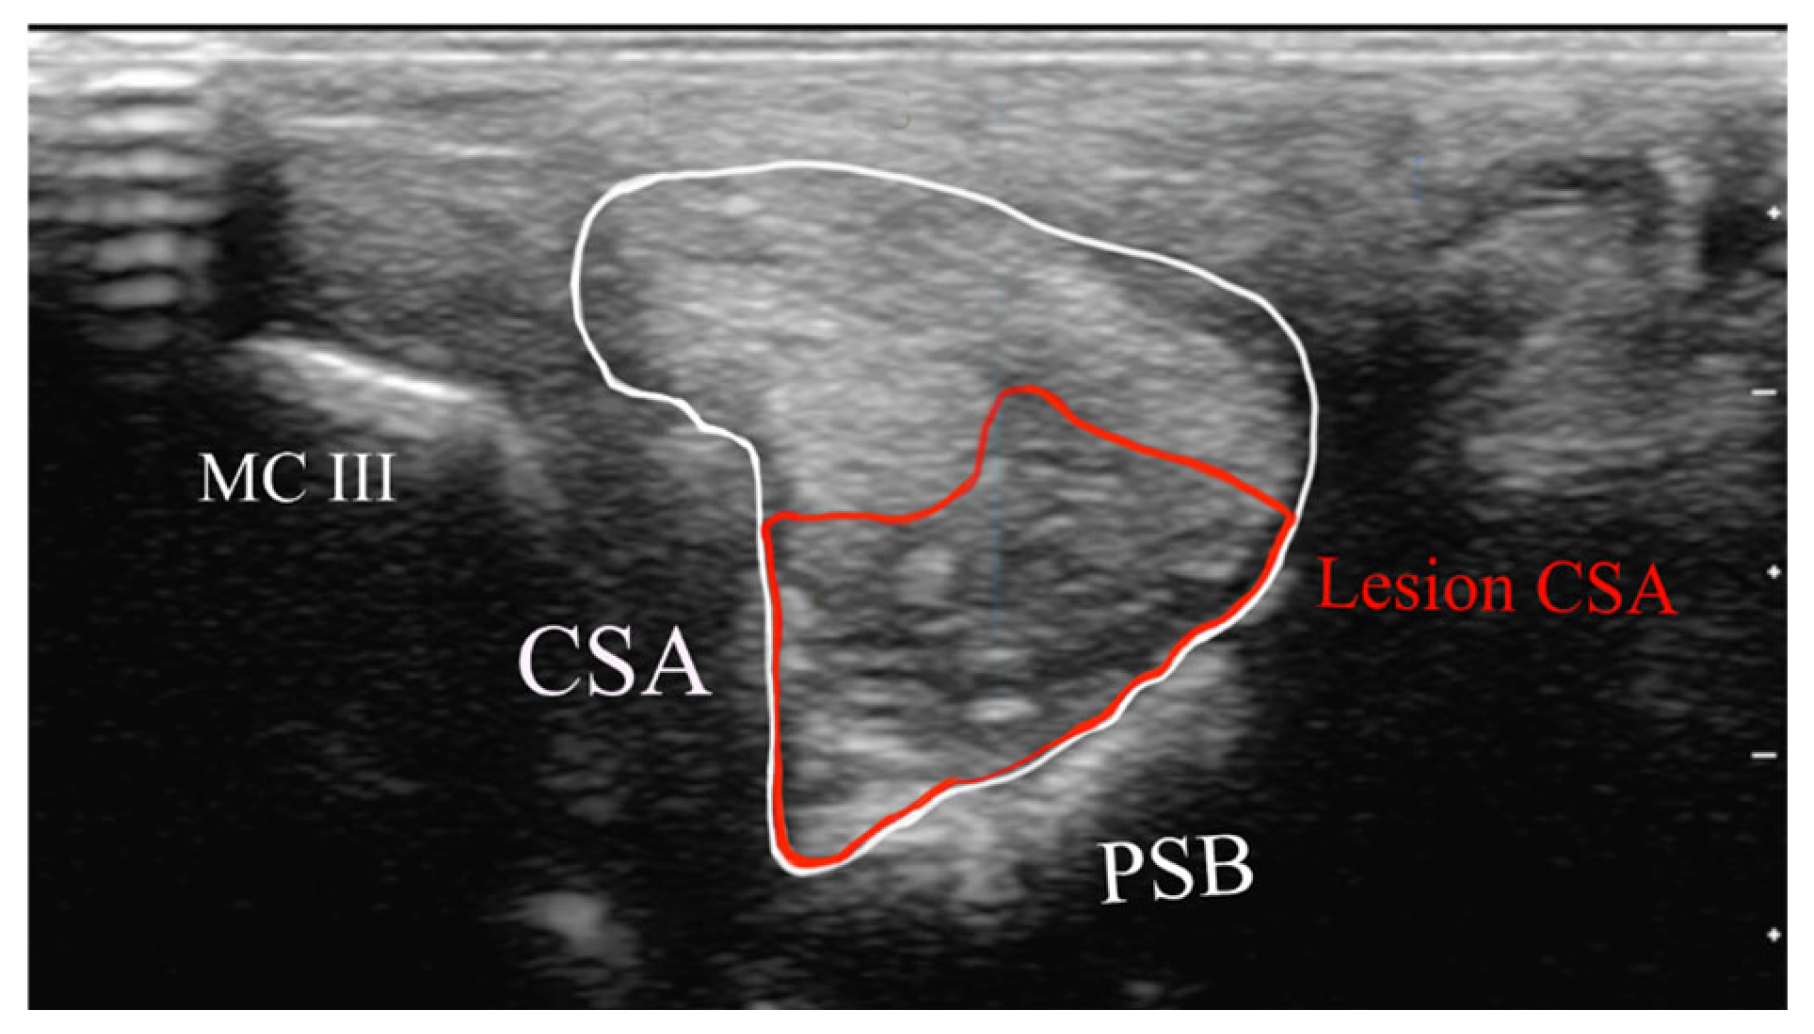

Measurements were performed by AB at the maximum injury level site from transverse images (Figure 3):

Figure 3. Measurements acquired from the transverse image at the maximal injury zone: cross-sectional area (CSA) of the suspensory branch (white), lesion CSA (red). PSB = proximal sesamoid bone. McIII = third metacarpal bone. There is a thin layer of echogenic tissue subcutaneously.

• Cross-sectional area of the SL branch (cm2);

• Lesion CSA (cm2).

Each measurement was repeated five times, and the mean value was calculated. The lesion CSA as a proportion of the total CSA was calculated and expressed as a percentage.

The mean CSA of affected branches was 1.99 cm2 (SD ± 0.07). The mean lesion CSA was 0.96 cm2 (SD ± 0.03). The lesion CSA as a percentage of the SL CSA had a mean of 21.0% (SD ± 0.96).